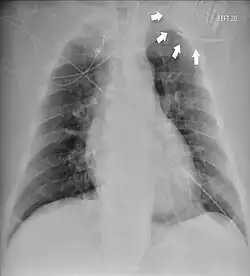

Chest radiograph showing twiddler's syndrome. The leads of the automated external defibrillator are wrapped around the device and can't be seen in the ventricle.

Given its speed and ability to provide a clear image of the lead coiling and device rotation, the chest X-ray is the most straightforward and important diagnostic tool for Twiddler's syndrome.[3]